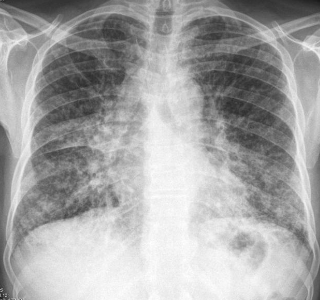

What is sarcoidosis?

Multisystem granulomatous disorder of unknown cause

Which demographic does scarcoidosis affect?

F > M

African Americans >>> Caucasians

Prior to 50 yrs

At the start of sarcoidosis, what are you expected to see?

Variable symptoms

Where would sarcoidosis be located?

Organ involvement most common

Lungs

Lymph nodes

Skin

Eyes

Salivary glands

What would a chest x-ray look like in sarcoidosis?

90% will show abnormal chest x-ray

In almost all cases of sarcoidosis, what kind of tissue is involved?

Lymphoid

Name the most common types of sarcoidosis

Lymphoid

Pulmonary

Cutaneous

Ocular

What other things can show up in sarcoidosis?

25% of people have ocular involvement

25% of people have skin lesions

What is the diagnosis of sarcoidosis?

Increased serum angiotensin-converting enzyme (ACE) levels which is mainly located in the capillaries of the lung but also in the kidney

Use a chest x-ray!

What is the treatment and prognosis of sarcoidosis?

60% of symptoms resolve spontaneously in 2 years

Corticosteroids if patients have progressive disease

5-10% succumb to disease and have further complications